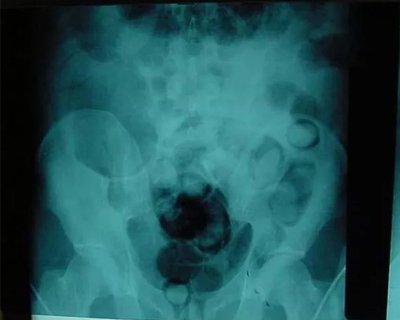

В Казахстане задержан гражданин Узбекистана, пытавшийся пронести марихуану внутри себя, пишет Пограничная служба комитета национальной безопасности Казахстана. Мужчина хотел перевезти на родину 13.5 грамм марихуаны.

При прохождении пограничного контроля, специально обученная собака учуяла наркотические средства у одного из лиц, проходящих контроль. В ходе личного досмотра и ручной клади никаких веществ обнаружено не было, однако при допросе выявилось, что гражданин Узбекистана перевозит 13.5 грамм высушенной марихуаны внутри себя.